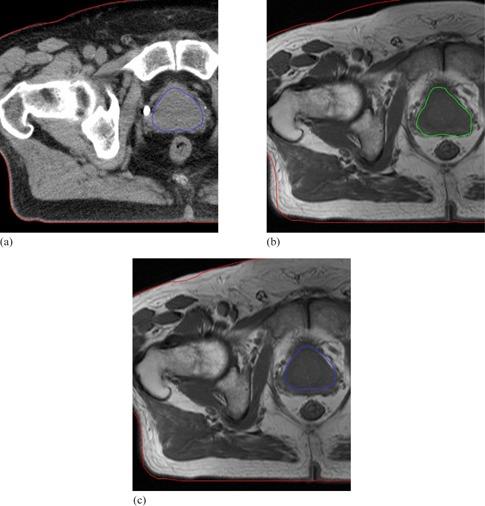

In recent years, a number of approaches have been applied to the problem of deformable registration validation. However, the challenge of assessing a commercial deformable registration system - in particular, an automatic registration system in which the deformable transformation is not readily accessible - has not been addressed. Using a collection of novel and established methods, we have developed a comprehensive, four-component protocol for the validation of automatic deformable image registration systems over a range of IGRT applications. The protocol, which was applied to the Reveal-MVS system, initially consists of a phantom study for determination of the system's general tendencies, while relative comparison of different registration settings is achieved through postregistration similarity measure evaluation. Synthetic transformations and contour-based metrics are used for absolute verification of the system's intra-modality and inter-modality capabilities, respectively. Results suggest that the commercial system is more apt to account for global deformations than local variations when performing deform-able image registration. Although the protocol was used to assess the capabilities of the Reveal-MVS system, it can readily be applied to other commercial systems. The protocol is by no means static or definitive, and can be further expanded to investigate other potential deformable registration applications.

近年来,已经有许多方法应用于可变形配准验证的问题。然而,评估商业可变形配准系统(特别是难以访问可变形变换的自动配准系统)的挑战尚未得到解决。我们使用一系列新颖和成熟的方法,为一系列 IGRT 应用开发了一种全面的、由四个组件组成的自动变形图像配准系统验证协议。该协议最初应用于 Reveal-MVS 系统,通过对不同注册设置的相对比较,通过后注册相似性度量评估来确定系统的一般趋势。通过基于合成变换和轮廓的度量,分别对系统的同模态和异模态能力进行绝对验证。结果表明,当执行可变形图像配准时,商业系统更倾向于全局变形而不是局部变化。虽然该协议用于评估 Reveal-MVS 系统的功能,但它可以很容易地应用于其他商业系统。该协议绝不是静态或确定的,并且可以进一步扩展以研究其他潜在的可变形配准应用。